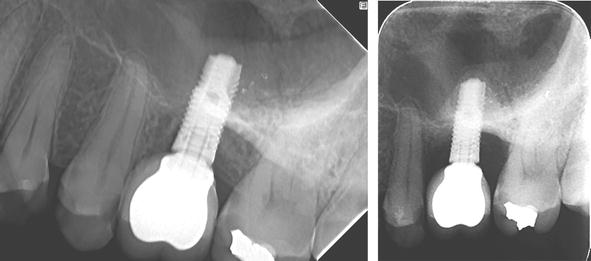

Literatura de specialitate arată că restaurările cimentate și cele fixate cu șuruburi pot oferi rezultate favorabile în ceea ce privește supraviețuirea implanturilor. Analiza complicațiilor biologice și tehnice evidențiază particularități distincte pentru fiecare metodă. În cazul restaurărilor cimentate, controlul excesului de ciment este esențial, deoarece reziduurile subgingivale pot favoriza inflamația periimplantară și pierderea osoasă crestală. Din acest motiv, principiile protetice implant dentar includ o atenție deosebită acordată poziției marginii de cimentare și tehnicii clinice utilizate.

sursa foto: intechopen.com